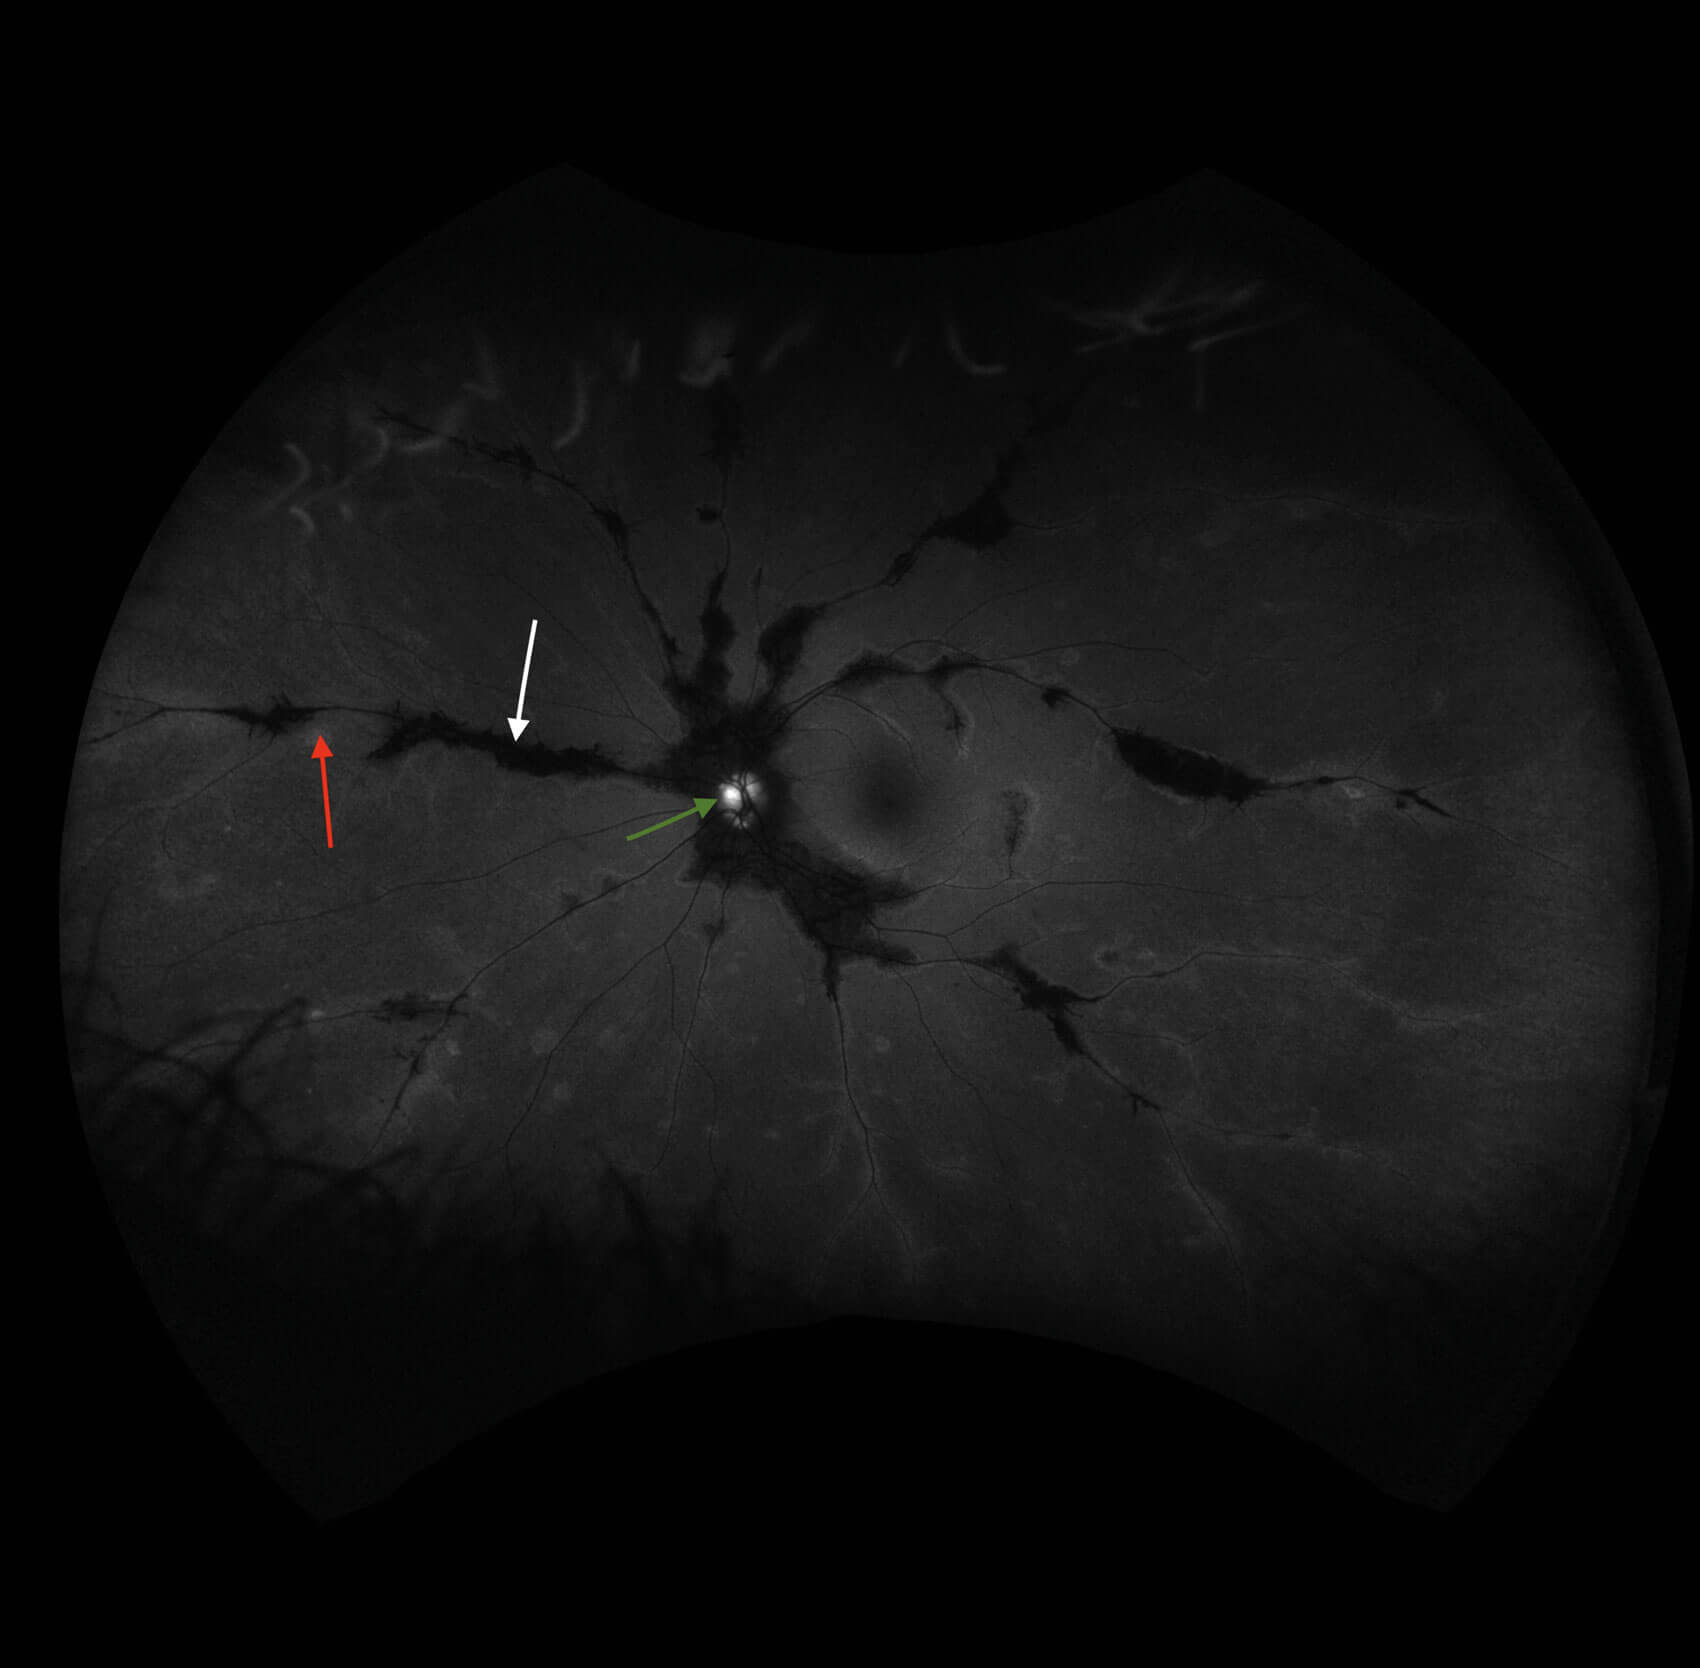

Widefield fundus imaging demonstrated these clinical findings (Figures 1a, 1b). Fundus autofluorescence showed hypo- autofluorescence in the areas of pigment accumulation and hyperautofluorescence in the areas of chorioretinal atrophy (Figures 2a, 2b). Fundus autofluorescence also showed hyper-autofluorescence at the optic disc indicative of optic nerve drusen. A 30-2 Humphrey visual field test revealed some defects superiorly paracentrally in the right eye. In the left eye there was a more significant field defect with an inferior and superior arcuate defect noted.

Figures 2a and 2b: Widefield fundus autofluorescence demonstrating hypo-autofluorescence in areas of pigment accumulation (white arrows), hyper-autofluorescence in areas of chorioretinal atrophy (red arrows) and hyper-autofluorescent optic nerve head drusen (green arrows).